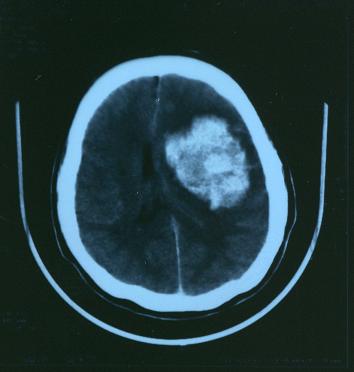

平成15年2

月

10

日の写真

中心のゆがんでいた部分が大分元のように戻って来ています。

又、この写真では良く判りませんが、細かい所に梗塞している箇所があります。